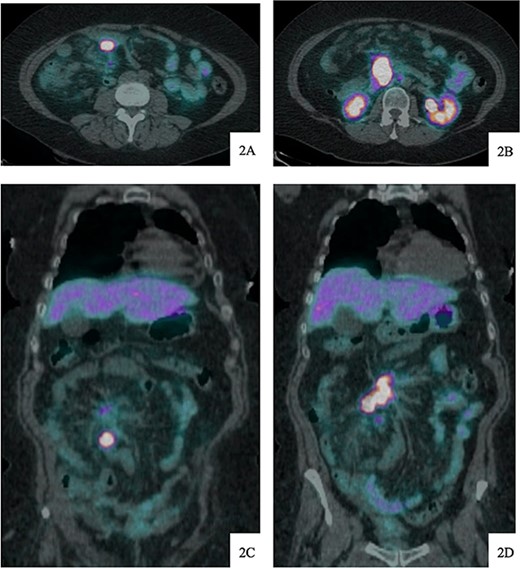

Upon arrival, she was afebrile with stable vital signs but appeared uncomfortable with significant abdominal pain. Her labs revealed leukocytosis, anemia, and absent lactic acidosis. CT demonstrated decreased enhancement and bowel wall thickening of several small bowel loops within the right lower quadrant, which were new compared to prior imaging (Fig. 4).

Contrast-enhanced axial CT image at time of presentation shows spiculated central mesenteric mass severe narrowing of the SMV with probably occlusion and encasement of the SMA with possible occlusion (A) associated with decreased enhancement and bowel wall thickening of several small bowel loops within the right lower quadrant (B). Coronal reformatting demonstrates the relationship of the mesenteric mass and affected small bowel (C).

Given her abrupt-onset abdominal pain in the setting of a tumor involvement of the SMA and imaging findings concerning for bowel ischemia, the decision was made to proceed with exploratory laparotomy after discussion regarding goals of care with the patient and her family.